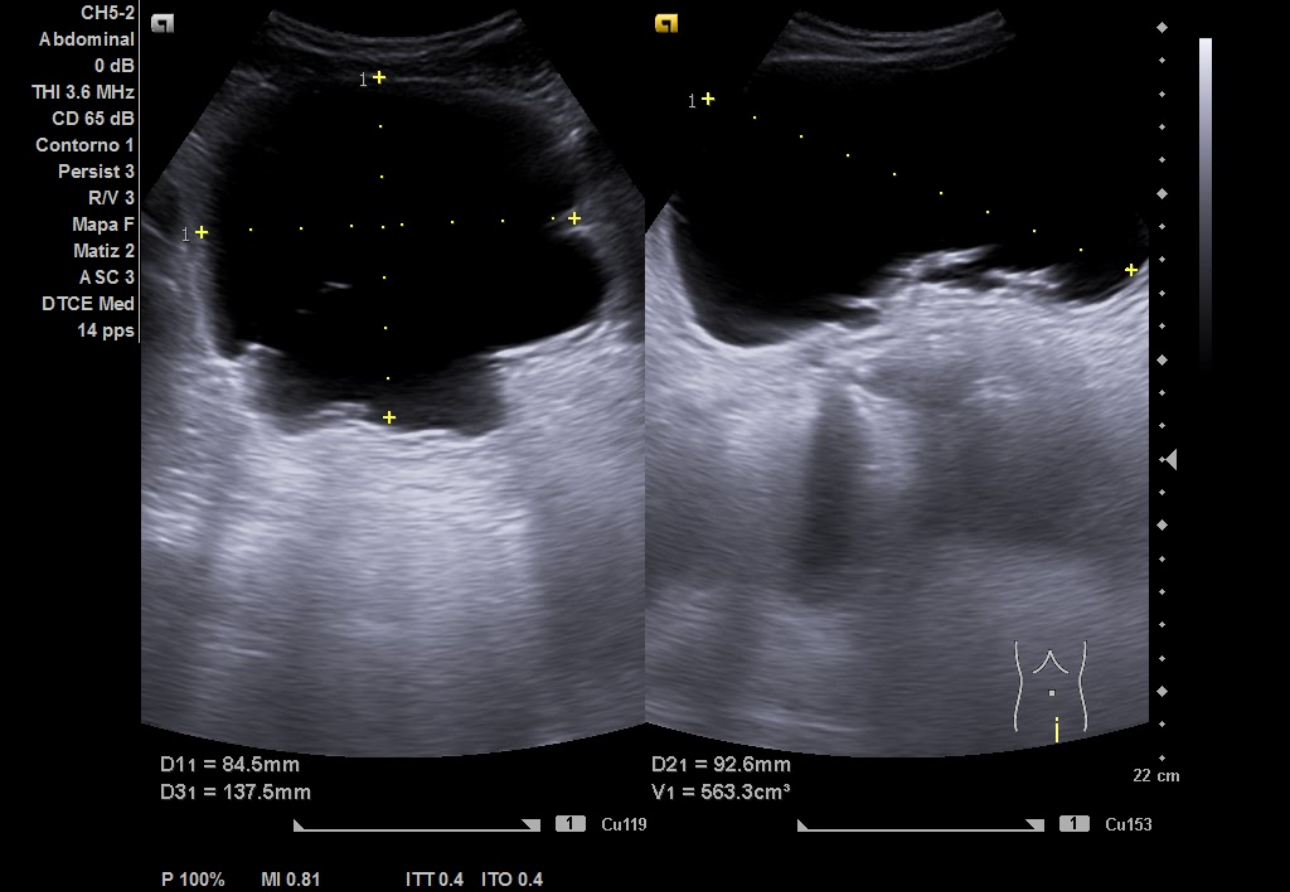

Ecografía aparato urinario en Centro de Salud: Riñones de tamaño normal, parénquima conservado con dilatación pielocalicial grado II-III izquierdo y grado II derecho. Vejiga con aspecto trabeculado, pared irregular con divertículos. Volumen premiccional 550 cc, postmiccional 450 cc. Volumen prostático de 50 cc.